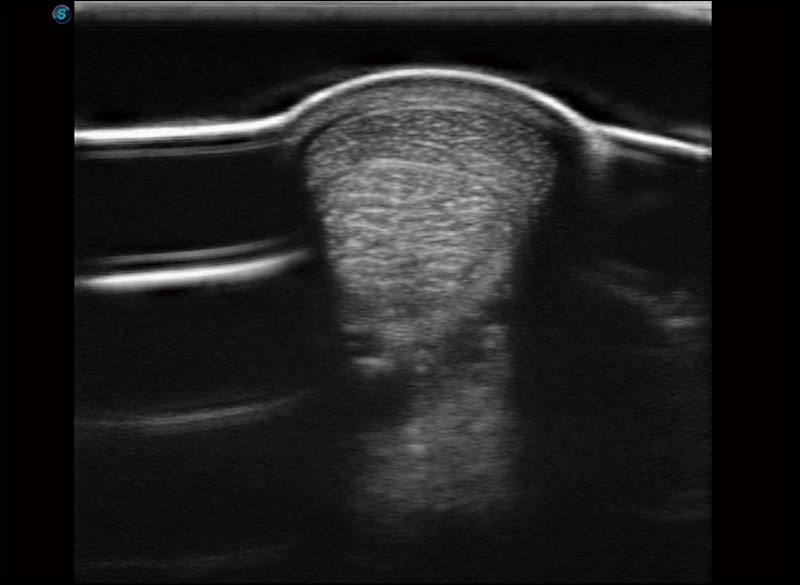

α1

精致轻巧 性能迅捷

α1卓越的图像质量和便捷的工作流程,使每位宠物医生都能轻松扫查。其全面的兽用应用功能和紧凑型的结构设计,可以满足动物检查的多种需要。专业的预设检查模式和多领域测量软件包有助于为不同类型的动物提供检查, 让宠物医生能够出色的完成工作。